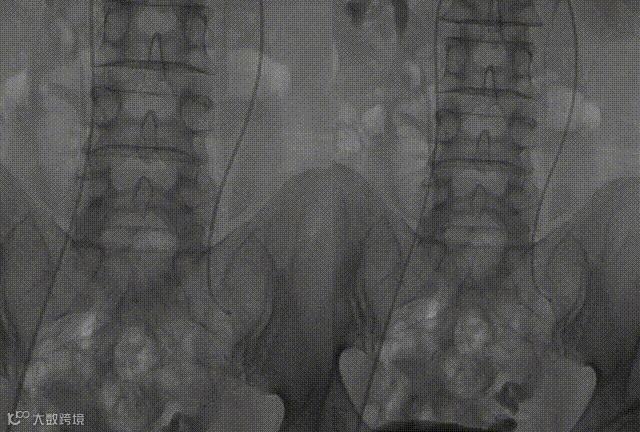

微导管选入扩张的血管分支内,注射1%充分泡沫化的聚多卡醇,手推造影显示:血流减缓。

使用微导管到达卵巢静脉病变处,置入2枚18系统8mm*20cm中天完全可控外周弹簧圈,再次手推造影剂未见静脉返流。

导丝配合单弯导管超选进入右侧卵巢静脉手推造影剂未见明显返流。